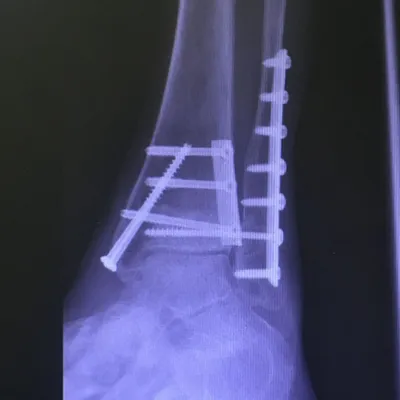

Preop and Postop ORIF Posterior Malleolus Fracture with associated Fibular fracture

Preop

Postop